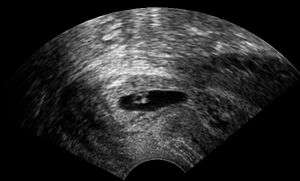

Vaginal ultrasonography of a cervical pregnancy at a gestational age of 5 weeks. See image below for details of the visible structures.[1] | |

The diagnosis is made in asymptomatic pregnant women either by inspection seeing a bluish discolored cervix or, more commonly, by obstetric ultrasonography. A typical non-specific symptom is vaginal bleeding during pregnancy. Ultrasound will show the location of the gestational sac in the cervix, while the uterine cavity is "empty". Cervical pregnancy can be confused with a miscarriage when pregnancy tissue is passing through the cervix.

- ↑ Agrell, Jesper (2014). "Ultrasonography of a cervical pregnancy". WikiJournal of Medicine. 1 (2). doi:10.15347/wjm/2014.011.